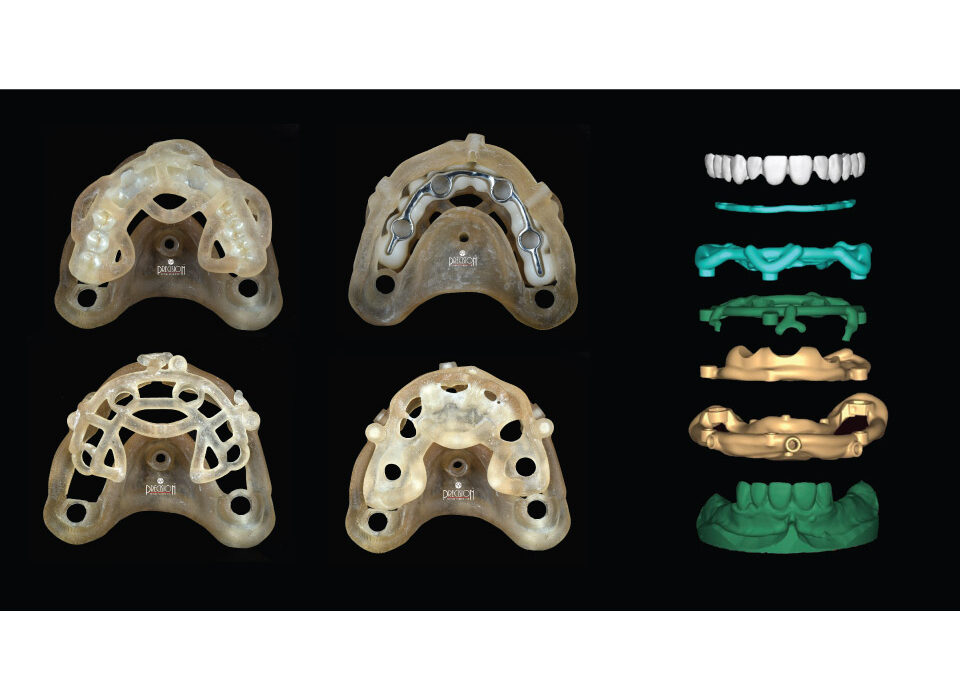

Digital Denture

A digital denture is a modern dental prosthesis created using advanced digital technology, including 3D imaging, CAD/CAM (computer-aided design and manufacturing) and 3D printing. Digital dentures offer improved accuracy, comfort, and aesthetics compared to traditional dentures. They also reduce the number of visits required and the overall treatment time.

Surgical Guides

Surgical Guide is a digital tool that ensures accurate positioning and angulation of implants, which is crucial for the success and longevity of the implant. We fabricate different types of surgical guides, including tooth-borne, mucosa-borne, and bone-borne guides i.e stackable.